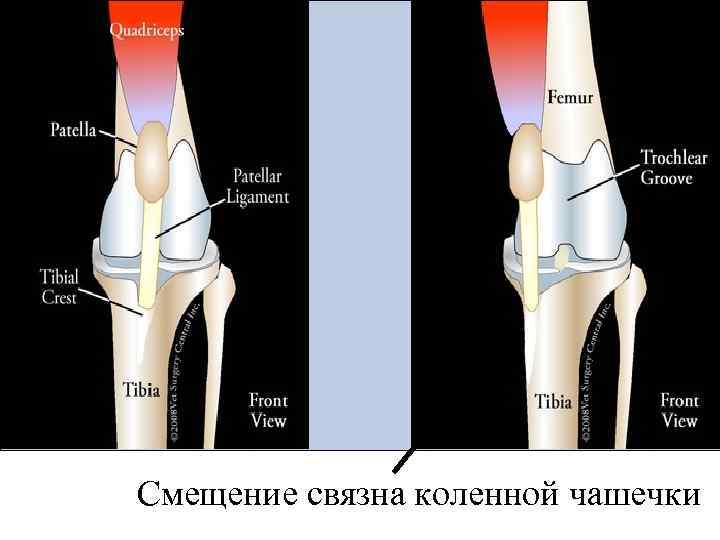

ВОПРОС № 80 - Вывих и перелом коленной чашки. • http: //handcent. ru/bolezni-kostnoy-sistemy/3061 perelomy-kolennoy-chashki-u-zhivotnyh. html

Смещение связна коленной чашечки

Лечение вывиха КЧ